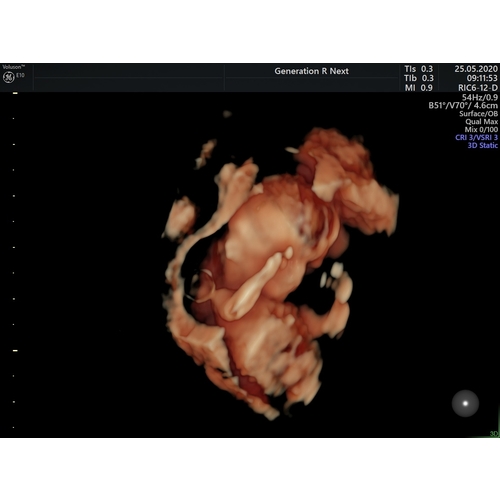

Mijn gynaecoloog heeft van een van de twee kindjes in m'n buik een 3D echo kunnen maken. Het andere kindje zat met de rug naar voor dus daar kon ze geen mooi beeld van nemen.

Dat zijn wel mooie foto's geworden! Gefeliciteerd met de tweeling! Super leuk!

Leuk! Ik doe ook mee aan generation r, maar ben nog niet uitgenodigd voor e ...